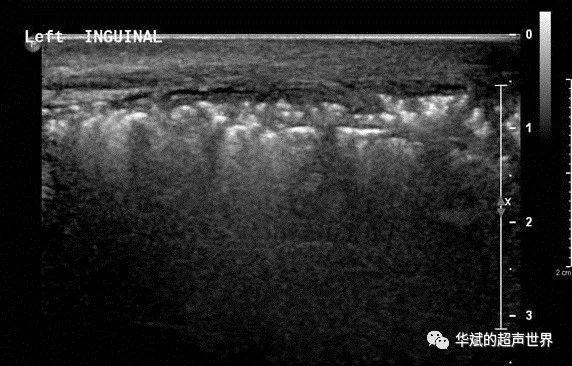

典型病例61福涅尔坏疽与气肿性睾丸附睾炎的鉴别坏死性筋膜炎气肿性